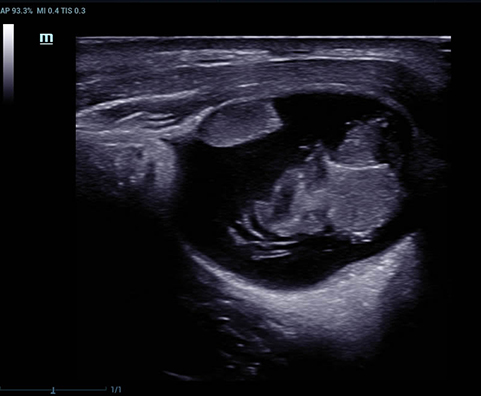

Sejak didirikan, Mindray terus mencari cara baru untuk meningkatkan keandalan diagnostik. Didukung Teknologi ZONE Sonography? terkini, platform ZST+ baru Resona 7 meningkatkan kualitas gambar ultrasound melalui pengambilan zona dan pemrosesan data saluran.

Selain kualitas gambar premium, Resona 7 juga meningkatkan kemampuan penelitian klinis dengan V Flow revolusioner untuk evaluasi hemodinamika vaskular, serta pengambilan penampang tercanggih dari rangkaian data 3D untuk diagnosis CNS pada janin. Kombinasi pengoperasian multisentuh berbasis gerakan yang paling intuitif dengan semua fitur klinis penting membuat Resona 7 menjadi gebrakan baru dalam inovasi ultrasound.